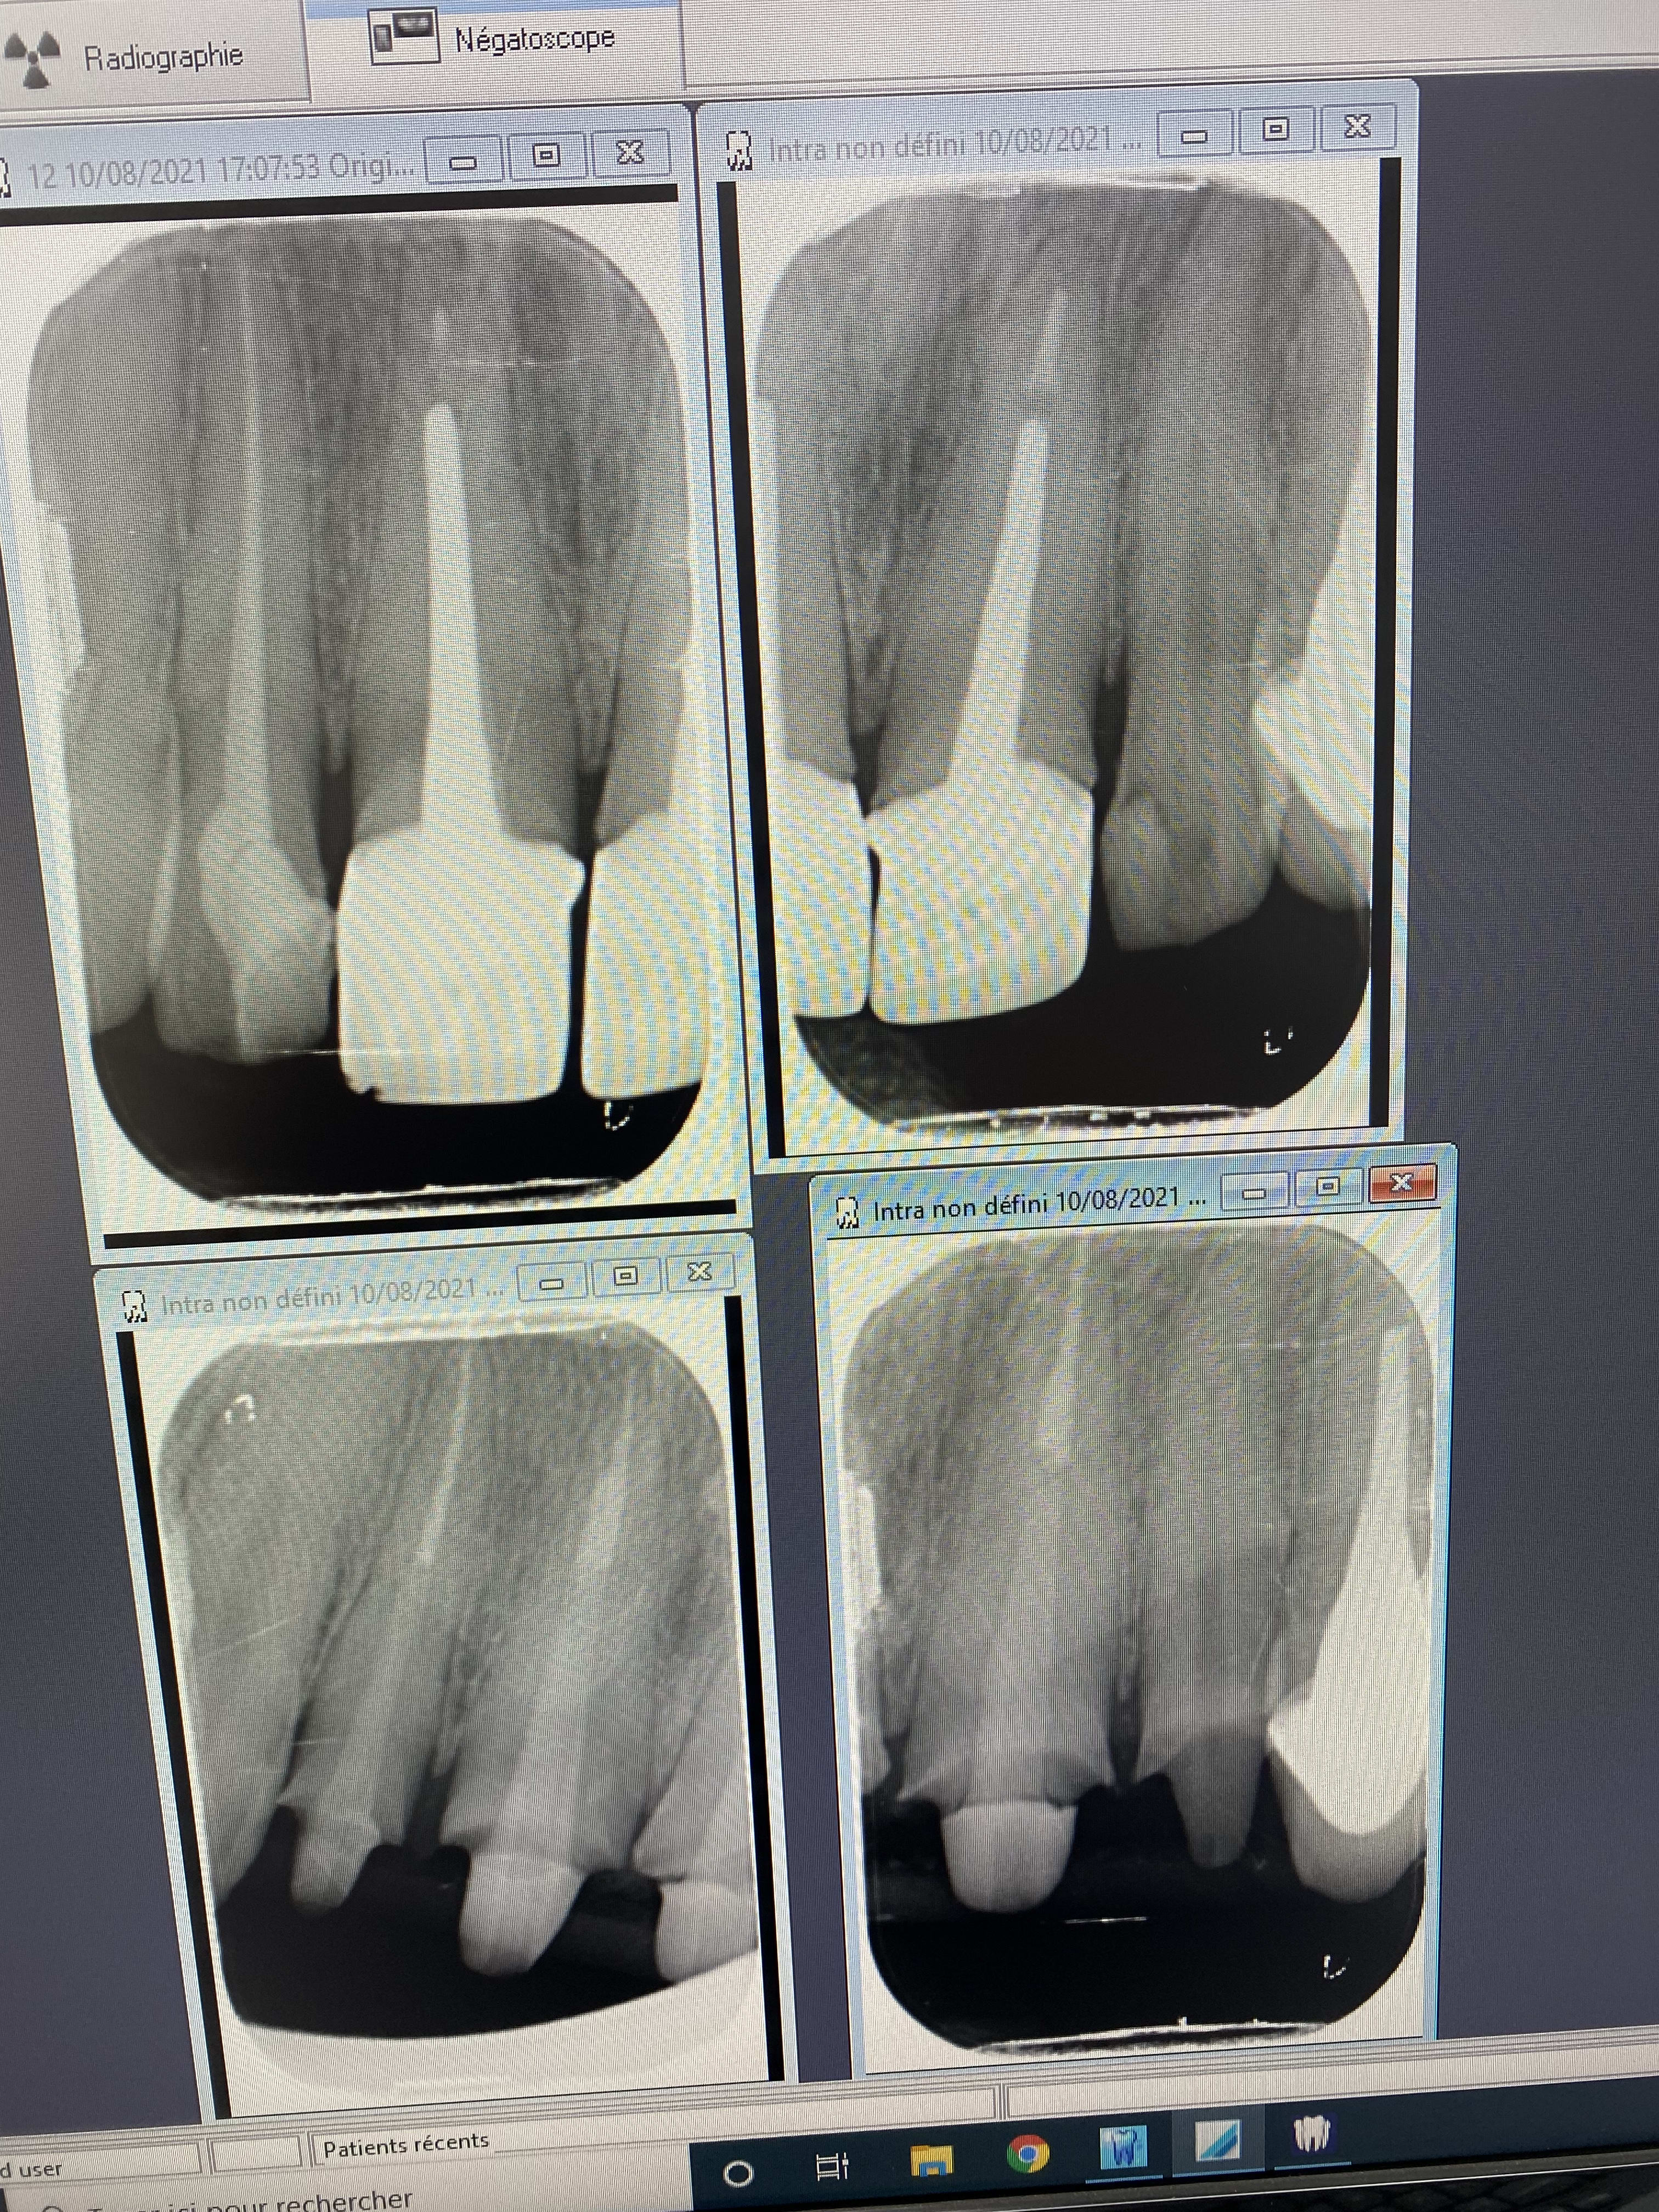

> Pendant que certains se les roulent à la plage, j'ai fait ça ce soir.

> Y'a plein de petits détails intéressants, dont la plupart avaient été anticipés

> à la radio, je me doutais évidemment que le localisateur serait inopérant vu la

> largeur des canaux, et j'imaginais bien que la majeure partie de l'alésage se

> ferait avec un gros foret à tenon.

> Mais ce que je n'avais pas anticipé, c'est que C ETAIT DES PUTAINS DE RICHEMOND

> DE L ENFER. 6 transmetals, 10 000 fragments et les nerfs en pelote avant même

> d'avoir commencé le boulot. Rincé.

On a les mêmes problématiques dis donc!!! Dépose mega pieux !!!! Rte rcr provisoire empreinte usinage .

Cas dont je suis fier, et qui m'énerve un peu.

Patiente que j'ai vaguement vue en 2019 pour 3 bricoles, rien de notable.

Un peu après le premier confinement (05 2020 donc), commence à ressentir des douleurs diffuses maxillo faciales; son généraliste lui prescrit des antibiotiques pour une sinusite.

Rebelote 6 mois plus tard, cette fois elle se rend aux urgences dentaires, qui ne voient rien et la renvoient vers un orl.

L'orl la voit, lui fait faire une irm, diagnostique un quelconque SADAM ou équivalent, lui prescrit de la gymnastique mandibulaire et , coup de chance en fait, lui dit d'aller voir ma gueule pour faire une gouttière.

Entre temps, re "sinusite", re antibios, re soulagement temporaire.

Bref, elle arrive ce soir pour une consult occluso/gouttière, et heureusement que je ne fais pas trop confiance à personne, je reprends tout du début.

Evidemment, aucun signe douloureux musculaire, ATM parfaitement fonctionnelles, mais une 37 qui ne réagit ni au froid, ni au fraisage, et finalement ni à l'ouverture de chambre.

1 an que ça durait ces conneries, pour un diag simplissime, ça pique toujours un peu. A mon avis, ça va vite aller mieux. On verra hein?